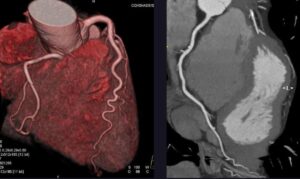

Ишемическая болезнь сердца является одной из ведущих причин инвалидности и смерти в мире. Частой ее причиной выступает стеноз коронарных артерий — сужение просвета сосудов, по которым кровь доставляет питательные вещества к сердечной мышце. Оценка степени развития стеноза очень важна и диктует выбор между неинвазивным лечением, например введением лекарств, и хирургическими вмешательствами, например установкой стентов. Современным «золотым стандартом» для выбора вида лечения являются значения нескольких гемодинамических индексов. Для их прямого измерения в клинике используются сосудорасширяющие препараты, и внутрь сосудов вводятся специальные ультразвуковые датчики. Междисциплинарной группой ученых из МФТИ, ИВМ РАН и Сеченовского университета предложен альтернативный способ оценки скорости пульсовой волны и эластичности сосудов без проникновения в организм и использования медикаментов. Результаты по апробации и использованию нейросети опубликованы в журнале первого квартиляMathematics.

Основные гемодинамические индексы — показатели работы сердечно-сосудистой системы: фракционный резерв кровотока, коронарный резерв кровотока и мгновенный безволновой коэффициент. Разработанная научной группой нейросеть позволяет настраивать параметры вычислительной модели с учетом индивидуальных особенностей пациента. Обучение нейросети проводилось на основе базы данных, содержащей характеристики так называемого «виртуального населения», то есть набор параметров, которые были рассчитаны с помощью нескольких тысяч вычислительных моделей, описывающих воображаемых пациентов различного возраста и пола, имеющих различную эластичность сосудов, частоту сердцебиения и периферическое сопротивление. Проверка нейросети была сделана на анонимизированных ретроспективных данных 100 реальных пациентов, проходивших обследование в Сеченовском университете, и такой подход позволил получить достаточно хорошую точность. Главное преимущество предложенного метода состоит в том, что он позволяет оценить такие трудноизмеримые параметры, как скорость пульсовой волны в аорте (волна повышенного давления) и эластичность сосудов, по широкодоступным данным, которые включают возраст, ударный объем, пульс, систолическое, диастолическое и среднее артериальное давление.

В итоге новый метод позволил повысить точность оценки фракционного резерва кровотока на 4%. Проведенные вычислительные эксперименты также показали, что гемодинамическая важность стенозов возрастает у пациентов с повышенной скоростью пульсовой волны в аорте до 10–15 м/с, которая связана со снижением эластичности ее стенок.